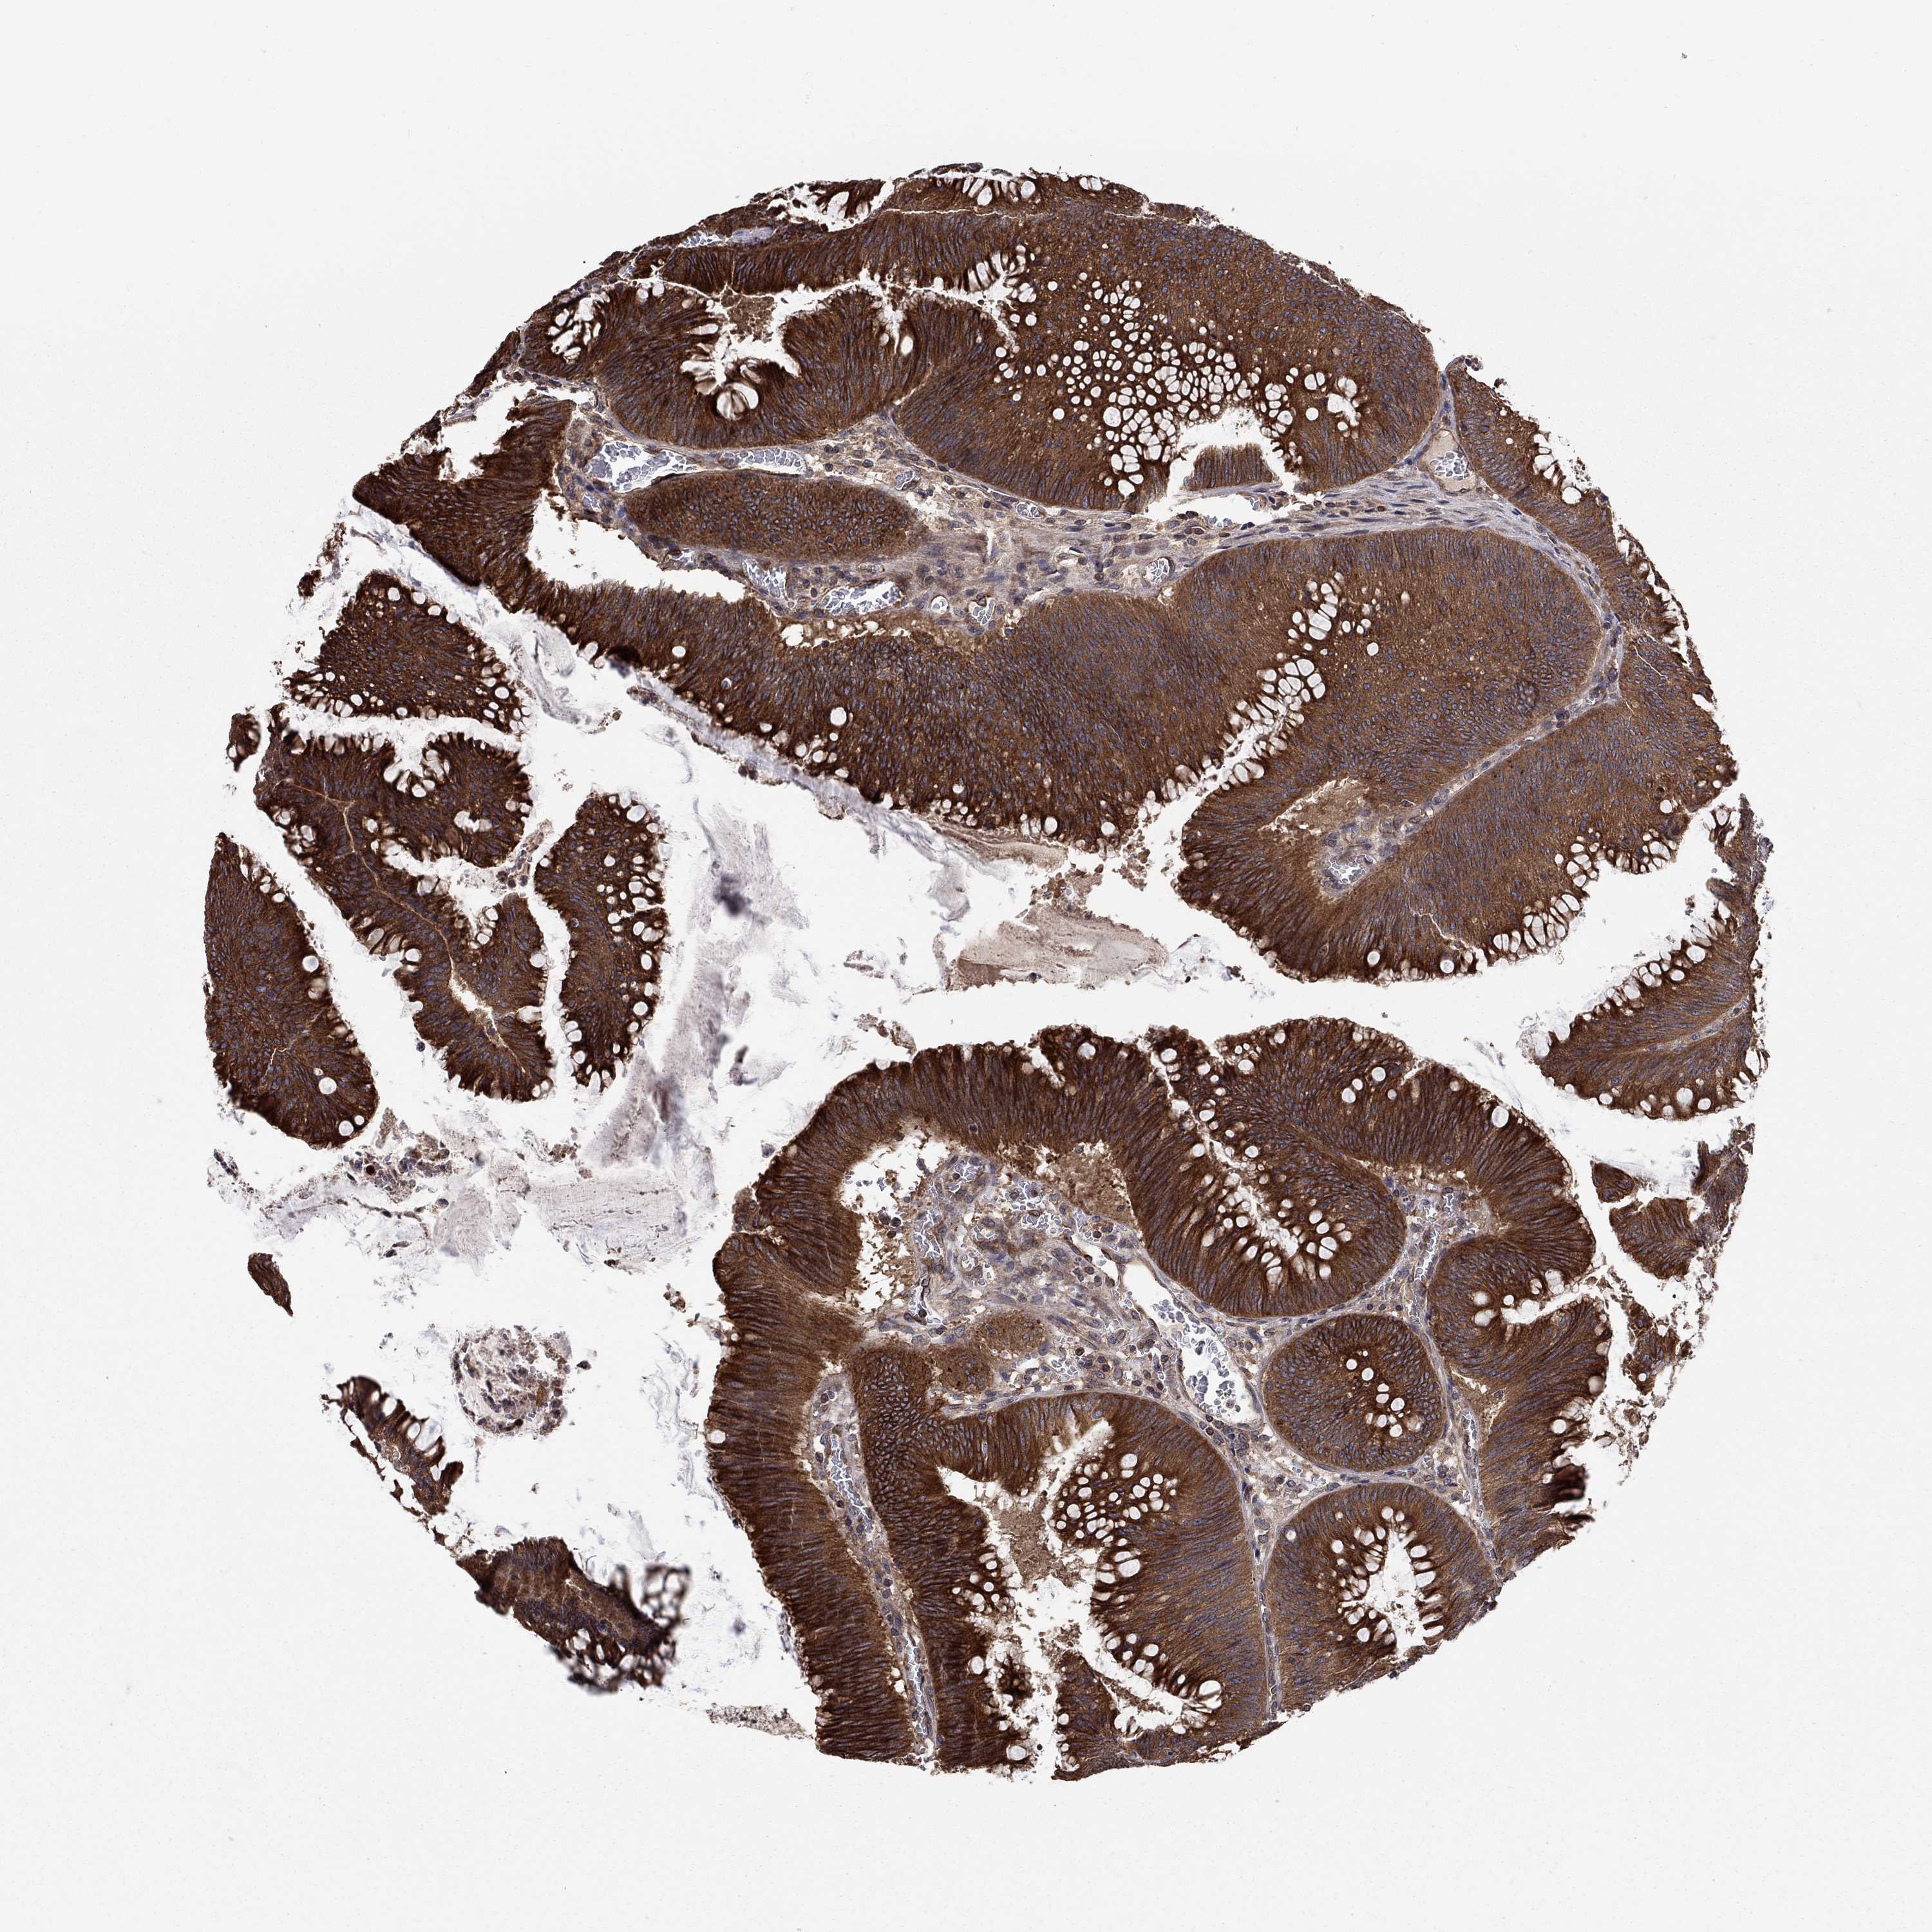

Colorectal cancer

Human cancer

Colon adenocarcinoma